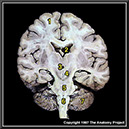

N1A5P10

23